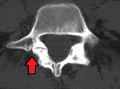

Spondylolisthesis L5/S1. Blue arrow normal pars interarticularis. Red arrow is a break in pars interarticularis